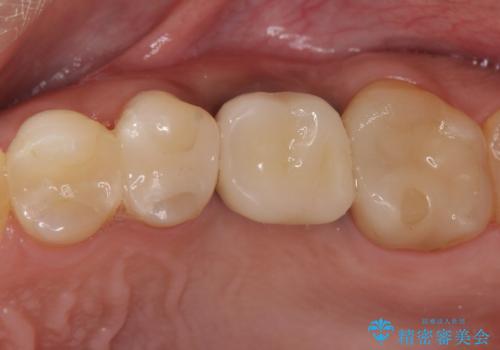

歯茎が腫れる インプラントでの治療

- 40代女性

- 10ヶ月

- 5-10回

- 左上5/インプラント:242,000円 骨増生:55,000円 カスタムアバットメント:110,000円 インプラント用仮歯:22,000円 ジルコニアクラウン:121,000円 合計550,000円費用は治療当時の料金となります